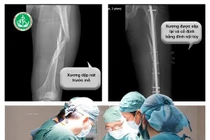

Khi đang chặt cây trong vườn của gia đình, bất ngờ cây đổ lệch hướng, dù cố gắng chạy nhưng nam thanh niên 23 tuổi vẫn bị một cành to đè trúng vùng đùi trái.